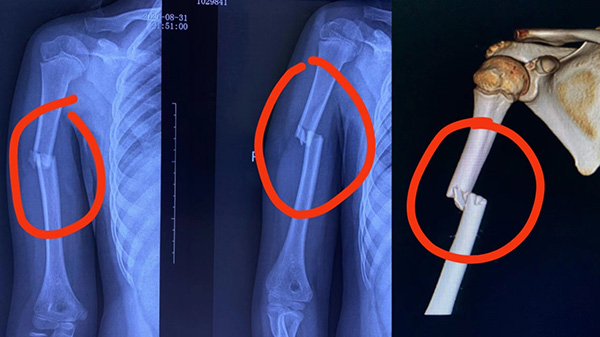

肱骨干骨折

肱骨干骨折指肱骨外髁頸以下1-2cm至肱骨髁上2cm之間的骨折。多發(fā)于骨干的中部,其次為下部,上部最少。當(dāng)肱骨中下1/3骨折時,易合并橈神經(jīng)損傷。